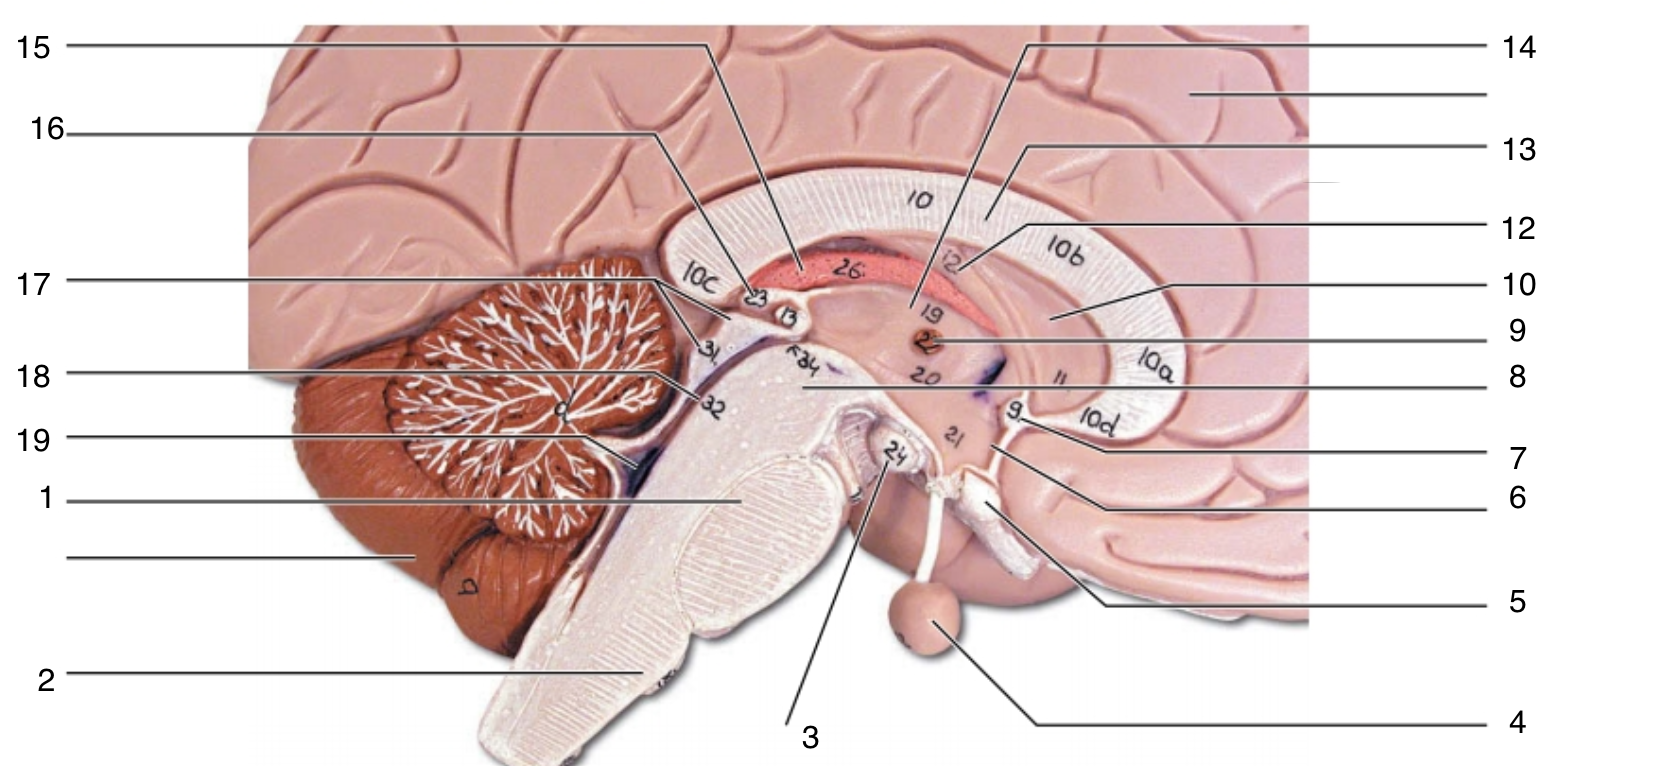

Brain Stem

1

pons

1

2

medulla oblongata

2

3

mammillary body

3

4

pituitary gland

4

5

optic chiasma

5

6

hypothalamus

6

7

anterior commissure

7

8

midbrain

8

9

interthalamic adhesion

9

10

septum pellucidum

10